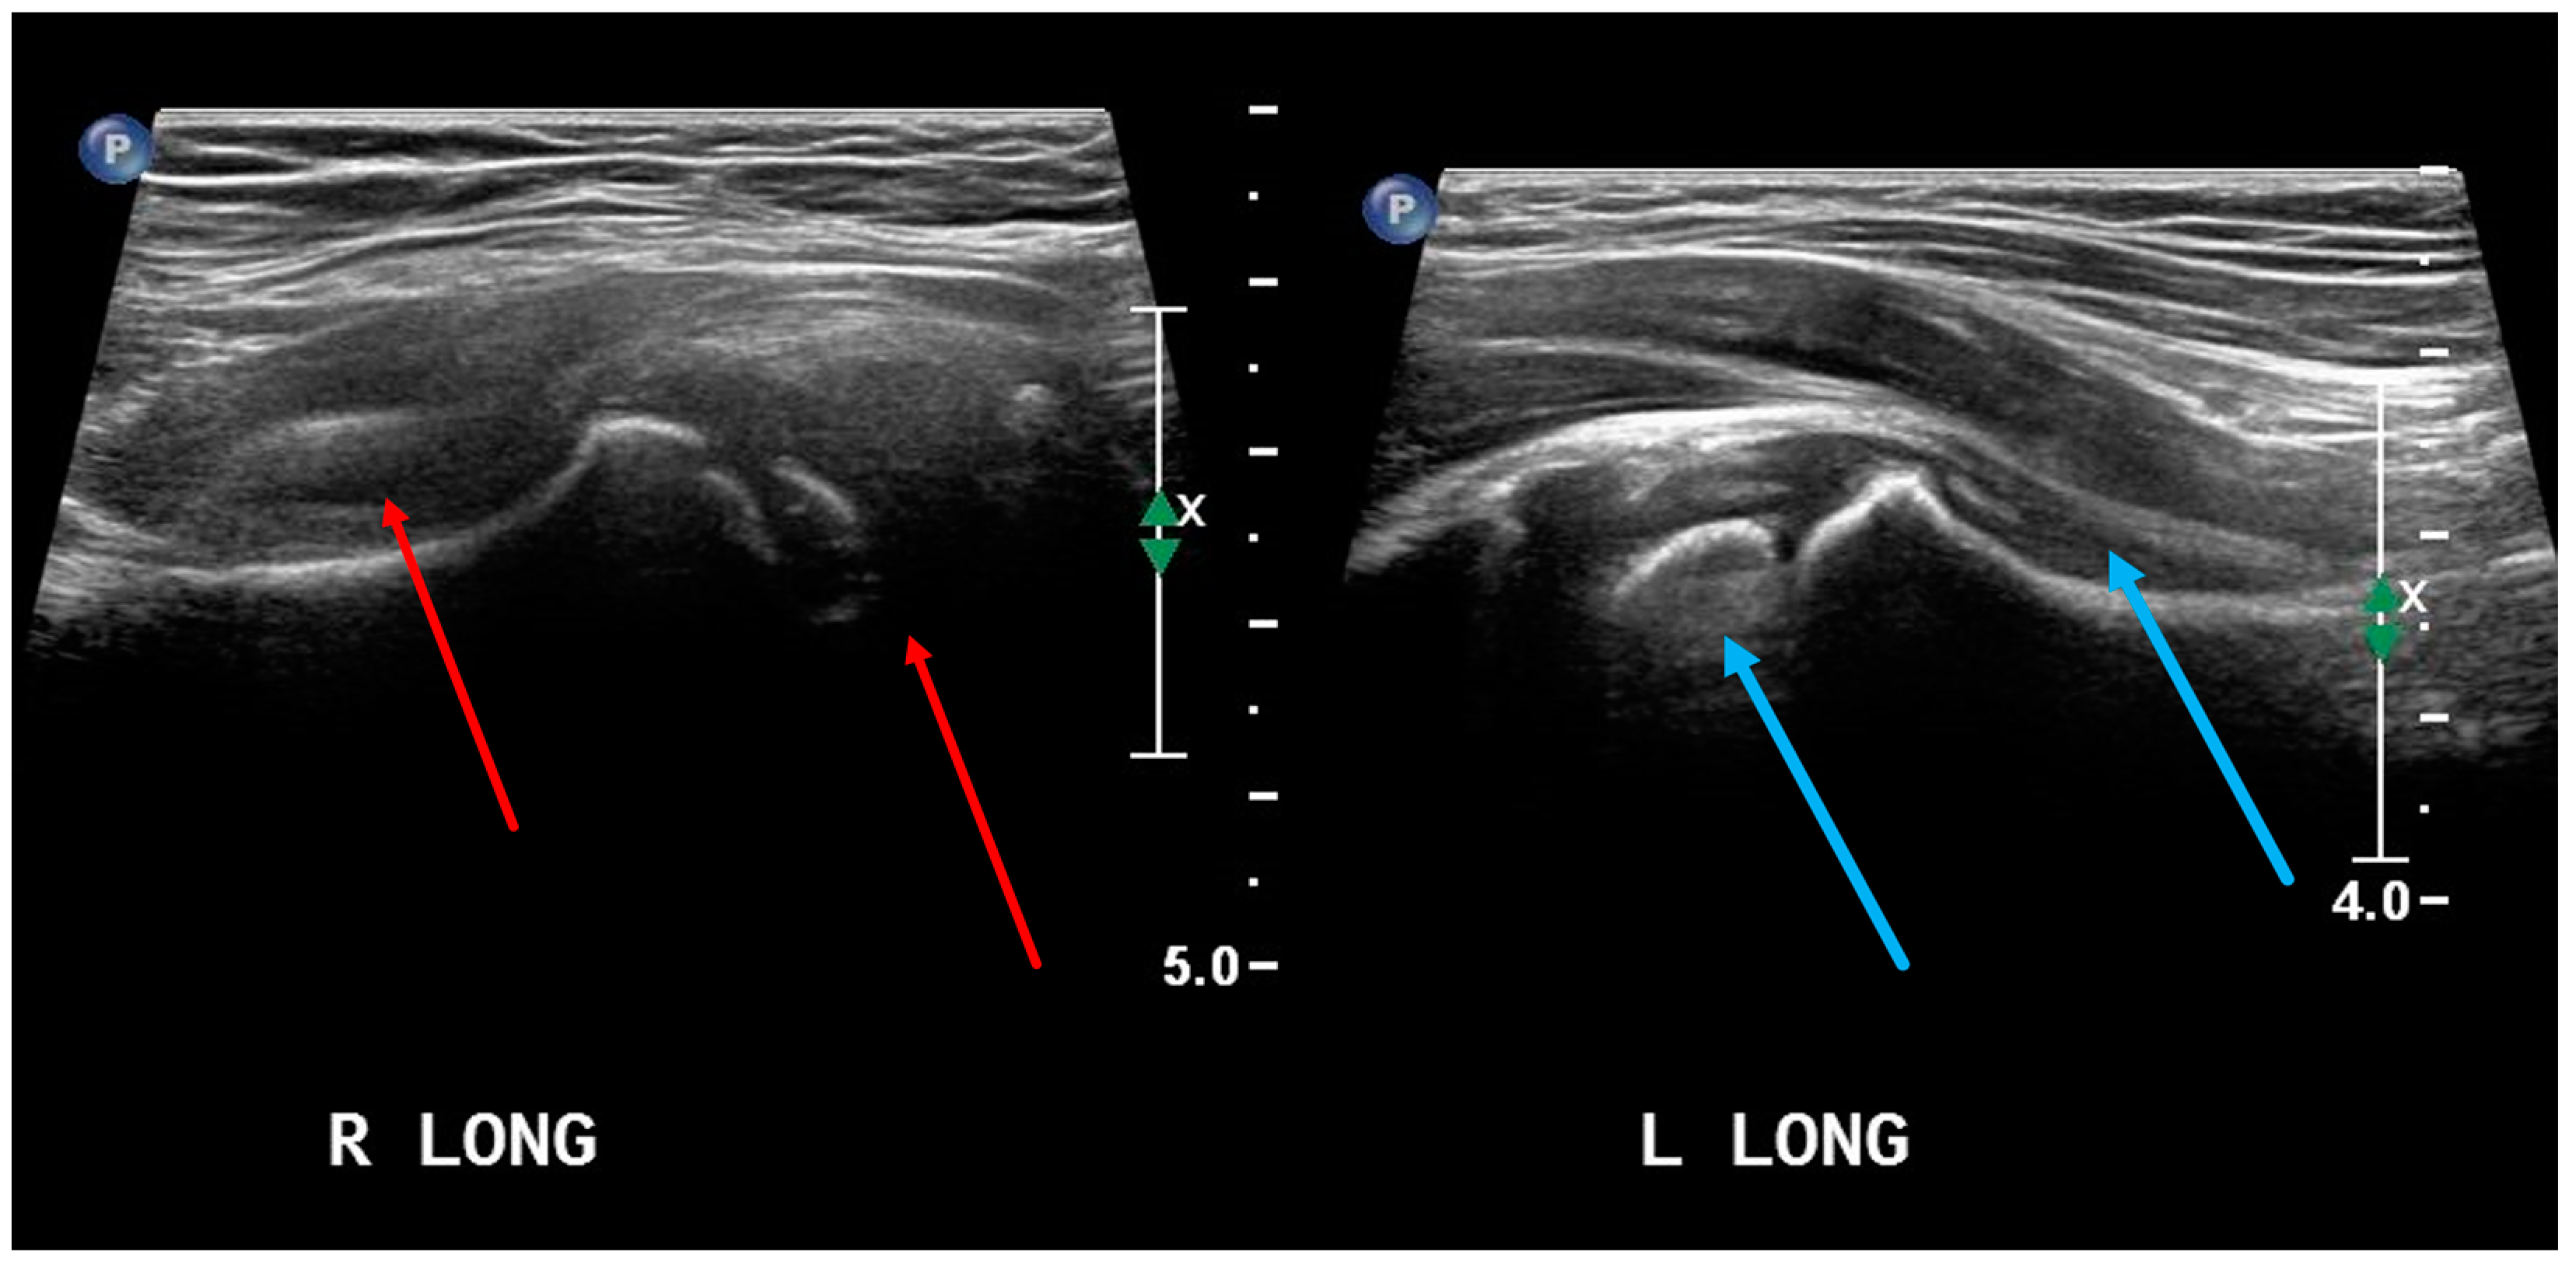

- Maruszczak, K.; Kochman, M.; Madej, T.; Gawda, P. Ultrasound Imaging in Diagnosis and Management of Lower Limb Injuries: A Comprehensive Review. Med. Sci. Monit. 2024, 30, e945413. [Google Scholar] [CrossRef] [PubMed]

- Czyrny, Z. Osgood-Schlatter disease in ultrasound diagnostics—A pictorial essay. Med. Ultrason. 2010, 12, 323–335. [Google Scholar] [PubMed]